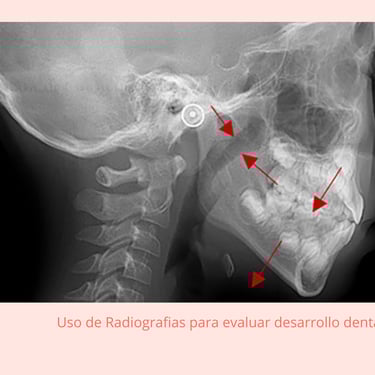

Evaluación Inicial: Examen y radiografías para evaluar el crecimiento y desarrollo dental.

Instrumentos: Radiografías, modelos dentales, exploradores.